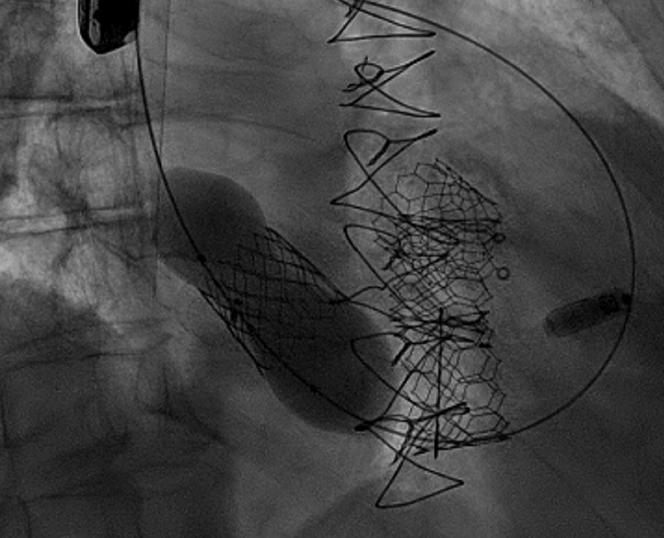

An 84-year-old man with a history of tricuspid valve regurgitation after repair with an incomplete annuloplasty band presented with worsening tricuspid regurgitation. He underwent a transcatheter valve-in-ring procedure, which was complicated by proximal valve embolization. The procedure was salvaged by performing an ad hoc caval implantation, followed by an additional valve implantation within the tricuspid band, with an excellent result.

一名84岁男性,既往因三尖瓣环成形带修复不完全后出现三尖瓣反流,此次因三尖瓣反流加重就诊。他接受了经导管瓣膜置入环内手术,术后出现近端瓣膜栓塞并发症。通过临时腔静脉植入术挽救了该手术,随后在三尖瓣环内额外植入了一个瓣膜,效果极佳。